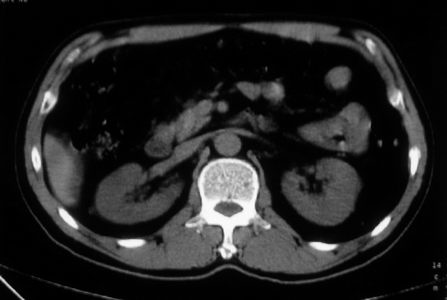

男,体查发现右肝低密度,右肾高密度结节影。高密度ct值92hu,囊肿?

肝右叶囊肿或血管瘤?右肾高密度囊肿。建议增强。

肝右叶圆形低密度灶,考虑囊肿或血管瘤,建议ct增强检查;右肾包膜下高密度圆形灶,考虑:囊肿并出血